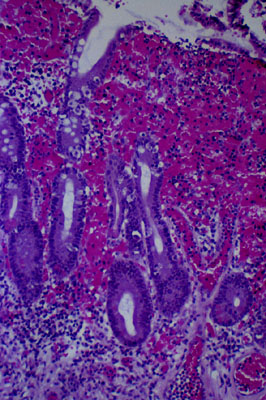

Stress ulcer of the stomach, histology

The superficial portion of the gastric mucosa is permeated with blood. The upper part of gastric mucosa is devoid of epithelial cells that have been lost due to ischemia.